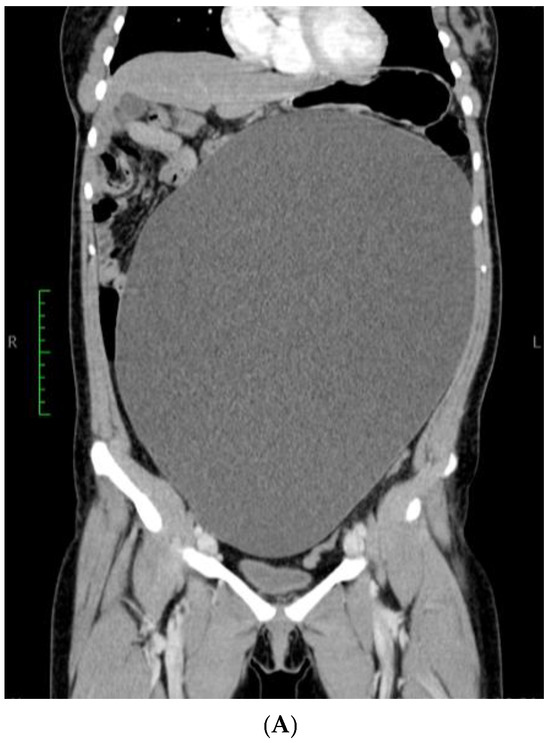

A 21-year-old, nulliparous, virgin woman presented to the Gastroenterology Department with the acute onset of upper abdominal pain but without any other symptoms such as chronic pain, abdominal distension, weight gain, or intra-abdominal pressure. She is a White/Caucasian woman from a rural environment with no medical history, and she lacked family history data. Moreover, the patient did not have any urinary or bowel symptoms. Her menstrual cycle was regular and normal, with her last menstrual period 3 weeks prior to hospital admission. Her full blood count was normal, and the microscopic examination of the urine sediment and urine culture did not show evidence of urinary tract infection. A urine pregnancy test was not performed due to the fact that she had never had intercourse. She had not received any treatment prior to the gynecological examination. The patient’s weight was 79 kg. Abdominal inspection mimicked a term pregnancy (Figure 1), and bimanual pelvic examination was not performed. Abdominal ultrasound performed at another medical facility revealed a simple cystic mass that was difficult to measure. No Doppler flow was detected, no septa nor papillary projections were noted, and there was no ascites. The left ovary appeared normal with only a 20 mm follicle. CA125, CEA, and CA 19-9 levels were within normal limits. The patient did not have immediate access to Magnetic Resonance Imaging (MRI), so she was referred for computer tomography (CT) examination which revealed a gigantic abdominal cystic mass of 150/300/360 mm (antero-posterior/transversal/cranio-caudal), most probably of ovarian origin with a thin wall with no septum or calcification that moves the retroperitoneal structures and compresses the bowel. The right ovary could not be observed. The left ovary measured 39/26 mm and presented few follicles, the largest being 26 mm. There were no abnormalities in the uterus, intraperitoneal fluid was absent, and no abnormal lymph nodes were identified. All other structures were within normal limits (Figure 2A,B).

Figure 2. CT Scan: Gigantic ovarian cyst of 360/300/150 mm. (A) Sagittal section and (B) coronal section.